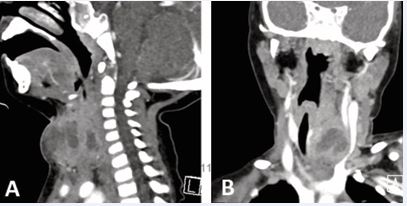

A 3-year-old girl presented with anterior neck swelling near the thyroid gland, slightly left of midline. CT revealed a 2.5 cm deep abscess within the SCM, with a hypodense tract traversing the left thyroid lobe (Figure 1A),and a suspected opening into the pyriform sinus (Figure 1B).

Figure 1 (A) Axial CT showing a left-sided abscess with a hypodense tract traversing the thyroid lobe, medial to major vessels. (B) Suspected internal opening in the left pyriform sinus (arrow).